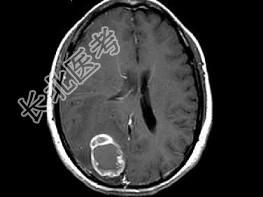

- 单项选择题女,46岁, 头痛、头昏半月入院,根据所提供图像, 最可能的诊断是 ( )

A、转移性乳头状腺癌

B、胶质瘤

C、脑脓肿

D、胶质母细胞瘤

E、毛细胞型星形细胞瘤